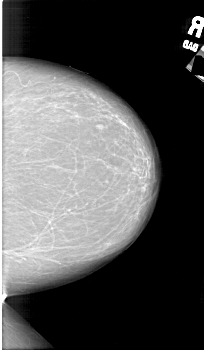

A_1802_1.RIGHT_MLO

RIGHT_CC LINES 6301 PIXELS_PER_LINE 3661 BITS_PER_PIXEL 12 RESOLUTION 43.5 NON_OVERLAY